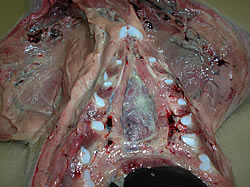

Las lesiones observadas en la necropsia muestran presencia de poliserositis (pericarditis fibrinosa, pleuresía y peritonitis fibrinosa, artritis).

Poliserositis

Pericarditis

Peritonitis

Artritis